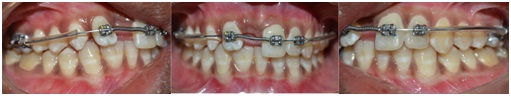

The 2 by 3 appliance is basically a modification of 2 by 4 appliances. The 2 by 4 appliance consists of two molar bands on the first permanent molars welded by a molar tube on its buccal side, four edgewise MBT orthodontic brackets bonded on incisors and a continuous arch wire to provide/maintain good arch form, as well as control the alignment of anterior teeth. The modified 2 by 3 appliance consists two molar bands, three Mc Laughlin Bennet Trevesi edgewise (MBT) orthodontic brackets, arch wire, sleeve and nickel titanium open coil spring [Table/Fig-3].

Orthodontic separators were placed in between contact points of 16, 15 and 26, 25. Bands were selected according to mesiodistal measurement of maxillary first molars, each band was welded by a molar tube on buccal side (Buccal Tubes Round Weldable, Nibha Dental Corporation) bands were cemented onto both maxillary first molars and brackets were bonded on maxillary incisors (Tehoo Mini MBT Brackets, .022inch Slot, Lot No 4112, manufactured by Libral Traders Pvt. Ltd) with adhesive (Solo, Universal Bond Enhancer, Lot no 5017637, Glendora, CA. Ormco, ENLIGHT, Light Cure Adhesive, Lot No 5067256, Glendora, CA). An aligning rectangle nickel titanium arch wire of. 016 X.022inch (N-Force, Nickel- Titanium preformed archwire, Made in USA) was placed.

An arch wire supporting with the sleeve between 16 and 13 on the right side and on the left side between 26 and 22 was placed (Classic orthodontics, USA). NiTi Open coil spring (. 010 inches, 3M, USA) was incorporated between 12 and 21 for space regaining [Table/Fig-4], then the arch wire was stabilized with ligature ties (3M Unitek, USA).